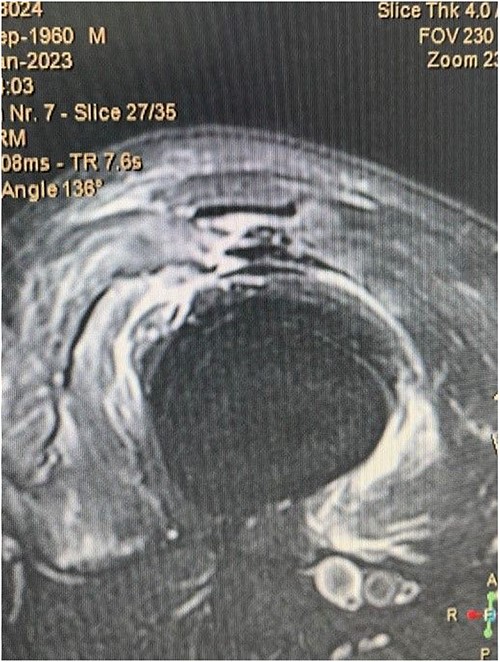

A 62-year-old male presented to emergency department of our hospital with complaints of low back pain and decrease range of motion of the right knee due to a fall from standing height. The patient was unable to weight bear and to perform a straight leg raise. His past medical history revealed no significant records. Clinical examination revealed a low back pain without neurological deficit and tenderness at right knee with a palpable defect proximal to the superior pole of the patella. Passive flexion of injured knee was measured as 110° and passive extension was full. Routine laboratory tests including white blood cells (WBC) count, erythrocyte sedimentation rate (ESR), c-reactive protein (CRP), liver and renal function were within normal ranges. The X-rays of the knee were normal without findings of patella baja and osseous pathology (Fig. 1), but the X-rays of the pelvis revealed bilateral sacroiliac arthritis. Based on this finding, further laboratory evaluation revealed a positive HLA-B27. An ultrasound scan performed externally showed a hypoechoic gap and quadriceps complete tear was noted. Magnetic resonance imaging (MRI) confirmed the findings seen on ultrasound with the difference that the rectus femoris (RF) was intact and there was a rupture of intermedius tendon (IT) combined with a partial rupture of vastus medialis. MRI sequences, especially T2W images revealed an intramuscular hematoma and discontinuity in the vastus IT (Figs 2 and 3). A small fluid filled defect, in the vastus intermedius just proximal to the insertion of quadriceps into the patella was also detected. The rectus femoris and vastus lateralis (VL) were intact. The defect in vastus intermedius measured ⁓5 cm from its patellar insertion.

Fat saturated T2 axial view showing the rupture of vastus intermedius and vastus medialis tendon.